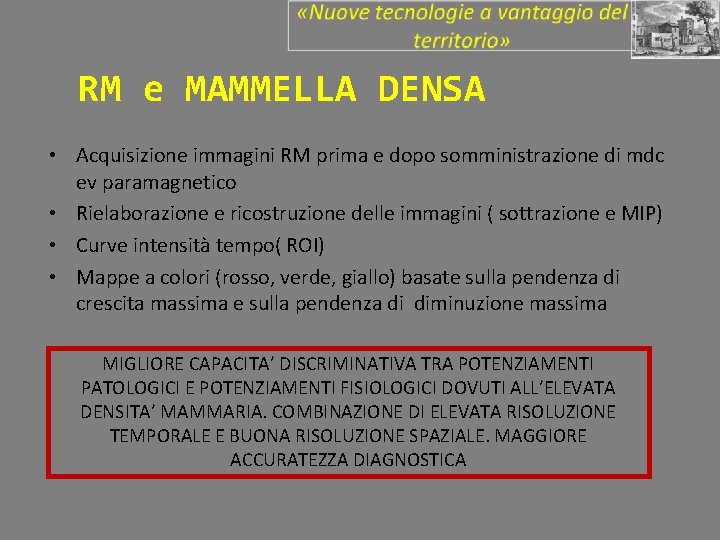

RM e MAMMELLA DENSA • Acquisizione immagini RM prima e dopo somministrazione di mdc ev paramagnetico • Rielaborazione e ricostruzione delle immagini ( sottrazione e MIP) • Curve intensità tempo( ROI) • Mappe a colori (rosso, verde, giallo) basate sulla pendenza di crescita massima e sulla pendenza di diminuzione massima MIGLIORE CAPACITA’ DISCRIMINATIVA TRA POTENZIAMENTI PATOLOGICI E POTENZIAMENTI FISIOLOGICI DOVUTI ALL’ELEVATA DENSITA’ MAMMARIA. COMBINAZIONE DI ELEVATA RISOLUZIONE TEMPORALE E BUONA RISOLUZIONE SPAZIALE. MAGGIORE ACCURATEZZA DIAGNOSTICA